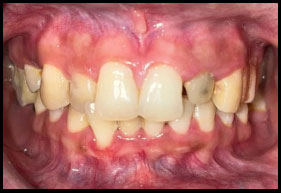

Peeso reamers (sizes 1 and 2) were used for post-space preparation, making sure that 3–4 mm of gutta-percha was retained at the apex. Next, a dual-cure resin cement was used to lute a prefabricated fiber-reinforced post into the canal (Fig. 3). Once the fiber post was in position (Fig. 4). Composite resin was then used to build up the core (Fig. 5). Occlusal view of the core build-up is shown in Fig. (6). Finally, a highly translucent all-ceramic crown was placed, restoring the tooth’s function and aesthetics in alignment with the surrounding dentition in occlusion (Fig. 7) and Occlusal view (Fig. 8).

Post operative.

Post operative - occlusal view.